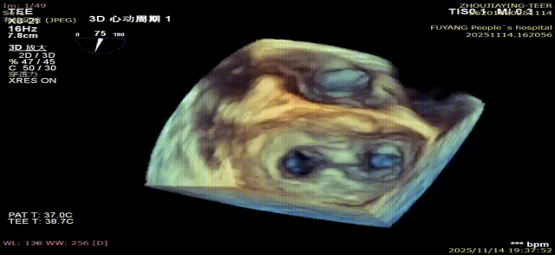

手术当日,在全身麻醉及TEE全程导航下,陈玺全副主任团队凭借丰富的临床经验与精湛操作技巧,顺利完成房间隔穿刺、瓣叶精准定位等关键步骤。针对患者二尖瓣A2/P2 区域反流靶点,团队精准夹合瓣叶,经X-plane技术与三维超声反复确认夹持质量后,成功释放一枚MitraClip XTR夹子。术后即时评估显示,患者二尖瓣反流由术前3 +重度降至轻度,平均跨瓣压仅3mmHg,手术达到预期效果,全程无并发症发生。

术后平均跨瓣压差3mmHg